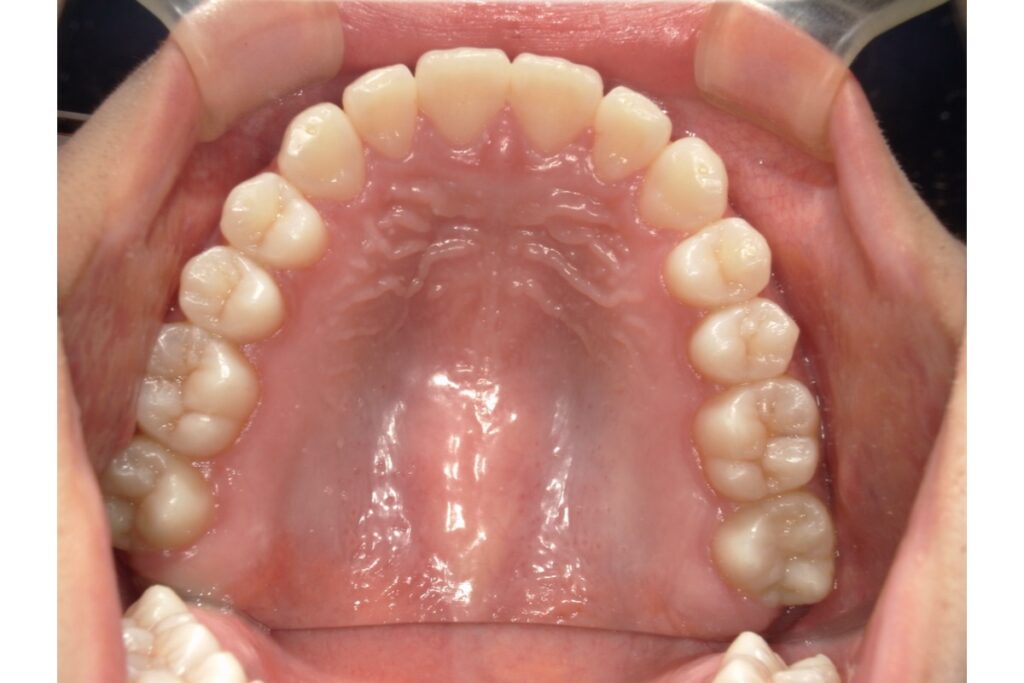

歯列のアーチとは、上・下の歯が並んでいるカーブの形のことです。

上から見たとき、歯が半円状に並んでいる様子をイメージしてください。

| U字型(広め) | 丸みのある緩やかなカーブ | 歯列が広く、笑顔が明るく見える |

| 楕円型 | 自然でバランスの良い形 | 多くの人の理想的な歯列形状 |